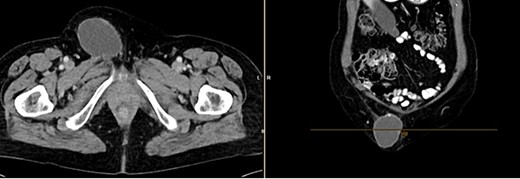

A month later, the patient presented again as the mass in the left groin area had increased in size. A CT (Fig 4) and another excision biopsy were performed. Histological examination revealed parts of a pleomorphic, most likely mesenchymally differentiated neoplasm. It was determined that the presence of a metastasis of the known prostate carcinoma could be ruled out. A myxofibrosarcoma was considered as a differential diagnosis, although the proliferation rate was rather low for this. Therefore, a reference pathology review was initiated.

CT of the abdomen from 26 July 2023: size-progressive metastasis in the left groin with infiltration of the adductor muscles; no dynamics in the primarily osteoplastic diffuse osseous metastasis.